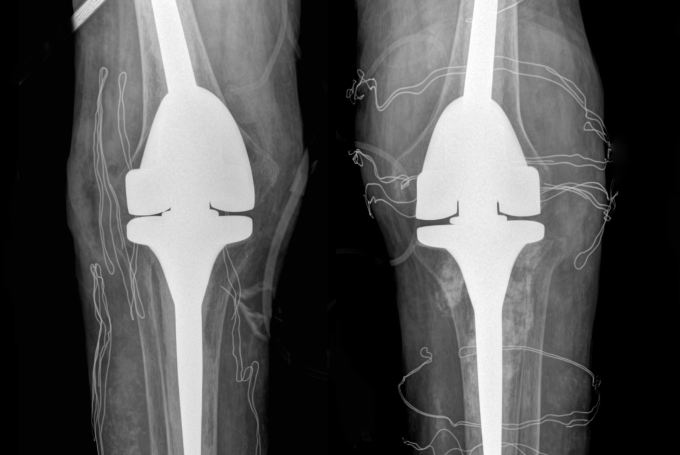

Phim chụp X-quang hai bên khớp gối nhân tạo của bệnh nhân. Ảnh: Bệnh viện Đa khoa Tâm Anh

ThS.BS Nguyễn Quang Tôn Quyền, Phó khoa Chấn thương Chỉnh hình, Bệnh viện Đa khoa Tâm Anh Hà Nội, chẩn đoán anh Tiến mất khả năng duỗi khớp gối, chỉ co được 60-70 độ, chụp X-quang cho thấy hai khớp gối bệnh nhân biến dạng nặng, tổn thương tophi khiến khớp và xương tiêu. Kiểm tra loại "thuốc" mua trên mạng mà anh Tiến uống, bác sĩ phát hiện là sản phẩm hỗ trợ sức khỏe đã bị Cục Quản lý Thực phẩm và Dược phẩm Mỹ (FDA) cảnh báo chứa chất dexamethasone gây nguy hiểm.

Êkíp bác sĩ loại bỏ các hạt tophi gây cản trở vận động, thay thế khớp gối đã tổn thương bằng loại khớp nhân tạo có bản lề, dành riêng cho bệnh nhân có các biến dạng khớp nghiêm trọng. Hậu phẫu, anh Tiến tiếp tục truyền thuốc ổn định nồng độ hormone tuyến thượng thận trong 2 ngày, sau đó duy trì uống thuốc hormone thay thế.